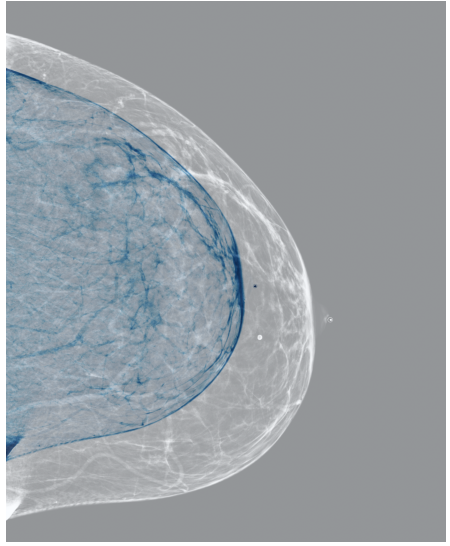

The EMBED and CSAW-CC datasets originally consist of images in DICOM format, which are converted into 16-bit grayscale PNG images for consistency and compatibility. Following the pre-processing procedure outlined in (Yala et al.,, 2021), we enhanced image quality and removed background artifacts—such as textual annotations commonly present in mammography images—by applying a contour detection procedure. All contours in the image are detected, and only the largest contour, corresponding to the breast tissue, is retained. This contour is then used to create a mask that isolates the breast region from the background. The isolated breast image is resized to a size of 1664×20481664\times 2048 pixels while preserving the aspect ratio. Finally, the resized image is normalized and converted to a 16-bit format.

Refer to caption

(a) FeatAlign

(b) FeatAlignReg

(c) ImgFeatAlign/ImgAlign

(d) FeatAlign

(e) FeatAlignReg